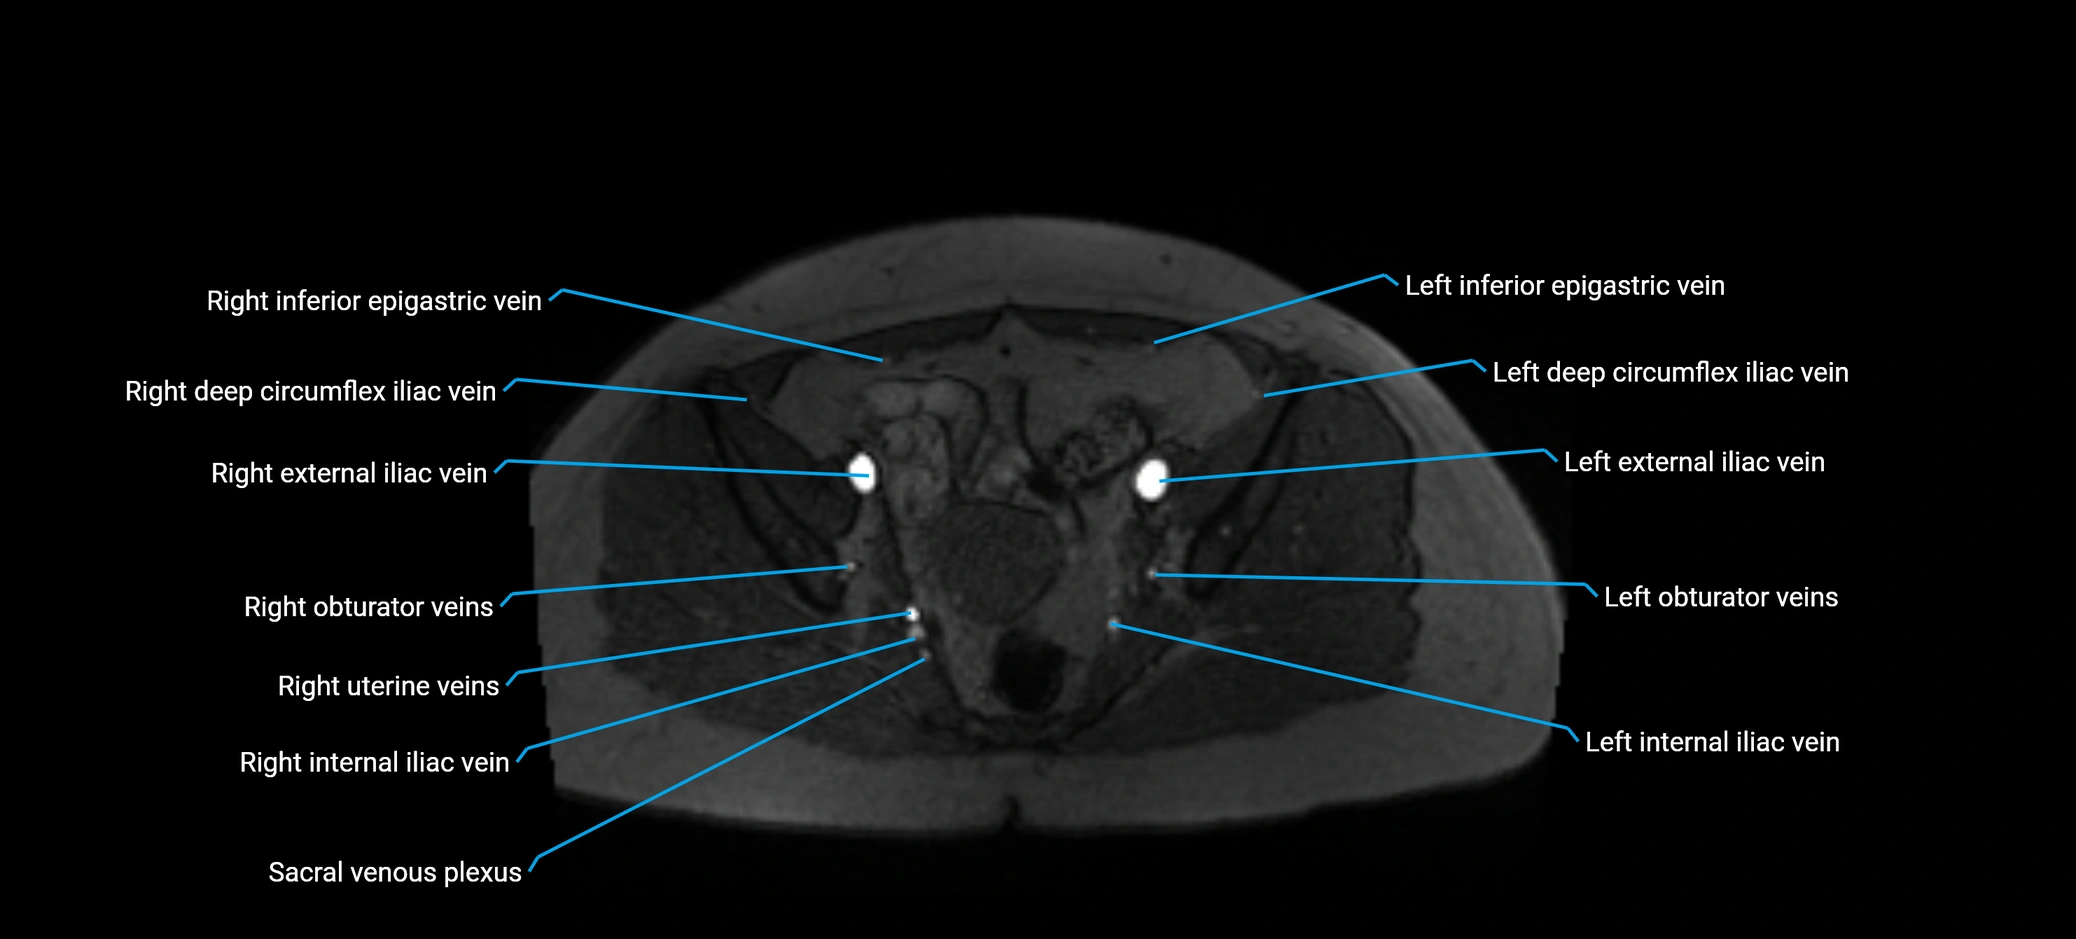

MRI image

image